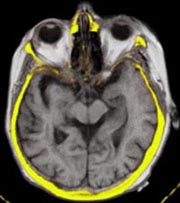

Mit Hilfe des LOCALITE iMRI Navigators können verschiedene Bildmodalitäten mit den interventionell

erhobenen MR-Daten koregistriert und fusioniert dargestellt werden.

CT: Die Koregistrierung von CT- und iMRI-Volumendaten erfolgt derzeit sowohl markerbasiert als auch

semiautomatisch auf Basis des Mutual Information Algorithmus. Für die fusionierte Visualisierung existieren

eine Reihe unterschiedlicher Darstellungen.